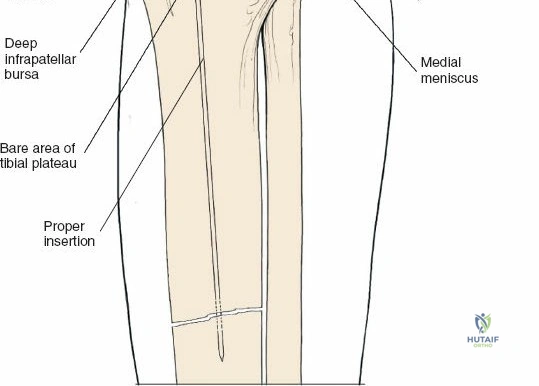

- Proximal Tibia: The preferred entry point for tibial nails lies in the proximal tibia, typically between the anterior tibial spine and the lateral edge of the patellar tendon. The infrapatellar fat pad (Hoffa's fat pad) must be navigated. Careful attention to the articular surface is paramount to avoid iatrogenic damage to the tibial plateau. The patellar tendon can be split or approached paratendinously, with long-term studies showing no significant difference in knee pain.

The incision should be adequate to allow clear access to the entry point and accommodate the targeting jig. The patellar tendon can be carefully split longitudinally or approached paramedially (medial or lateral to the tendon). - Entry Point Determination: The ideal entry point is crucial for proper nail alignment and preventing iatrogenic damage. It is typically located on the anterior cortex of the tibia, just medial to the lateral edge of the patellar tendon, distal to the articular surface of the tibial plateau.

- Fluoroscopic Guidance: Use an Awl or K-wire under AP and lateral fluoroscopy to confirm the entry point. The AP view should show the wire positioned to align with the central axis of the medullary canal. The lateral view should show the wire in line with the anterior cortex, avoiding a posterior entry which can damage the posterior cortex and lead to malalignment.

- Patellar Tendon Protection: Ensure the entry reamer or awl does not scrape the posterior aspect of the patella or damage the articular cartilage.

- Once the entry point is accurately localized, a cannulated awl or bone awl is used to open the cortical bone.

A K-wire is then passed into the medullary canal.